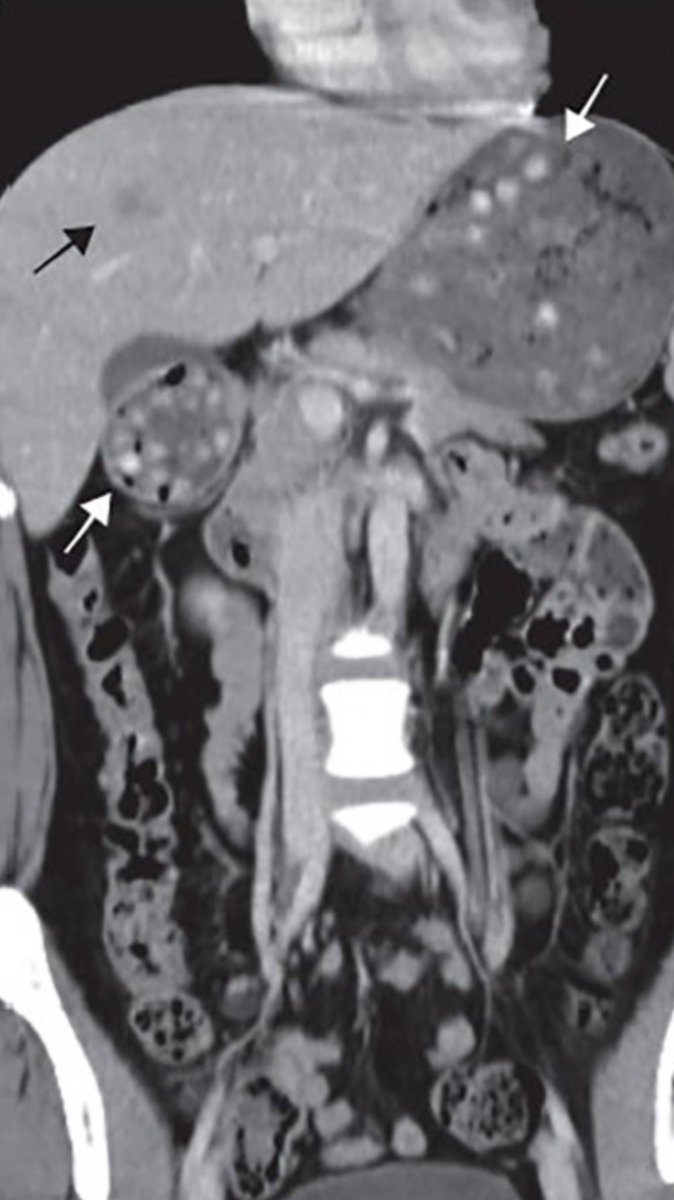

On my last #EM shift, my resident showed me this interesting #CTScan from Kao et al. If you ever wondered what #boba looks like in your stomach and duodenum, check out the white arrows PMID: 32995185